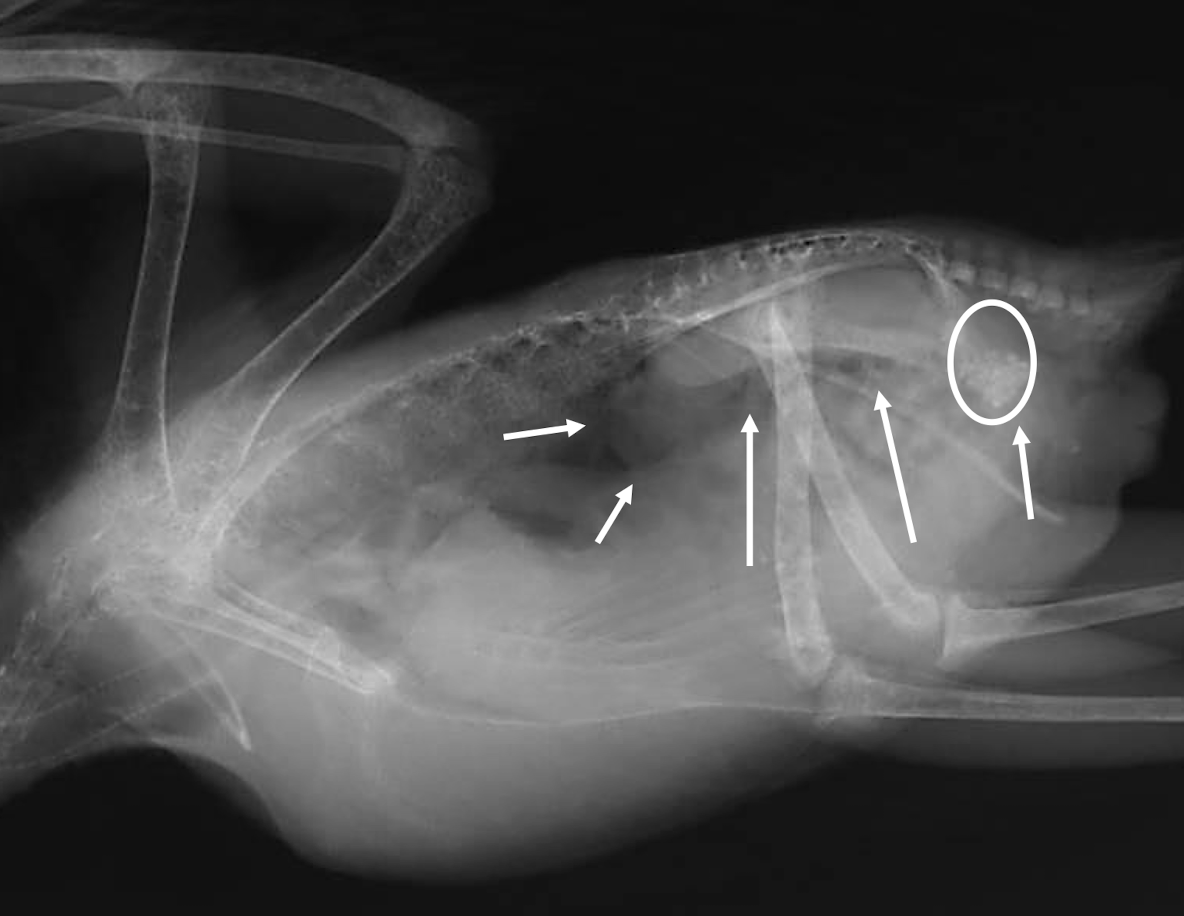

Whats wrong?

pneumonia

Bacterial airsacculitis → thickening of airsac wall

Fungal airsacculitis